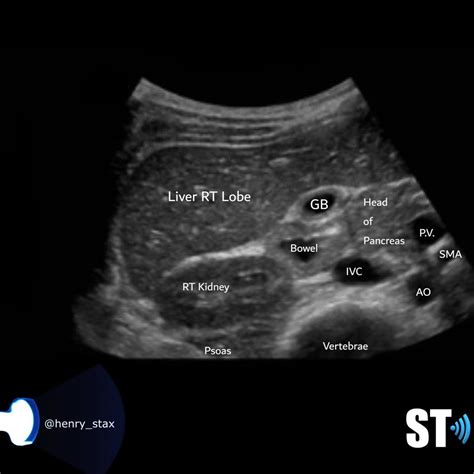

What Does a Normal Liver Ultrasound Look Like?

A radiologist interprets the scan by evaluating several key characteristics of the liver tissue and surrounding structures. When a report states a normal liver ultrasound, it means the following findings were observed:

Feature Expected Normal Finding

Size The liver should be of normal proportions, not enlarged (hepatomegaly) or shrunken (atrophy).

Echogenicity The texture should be uniform and slightly brighter than the adjacent kidney cortex.

Contours The edges should be smooth, not irregular or nodular.

Vessels Hepatic veins and the portal vein should be visible, patent, and show normal blood flow patterns.

Biliary Ducts Should not be dilated or obstructed.